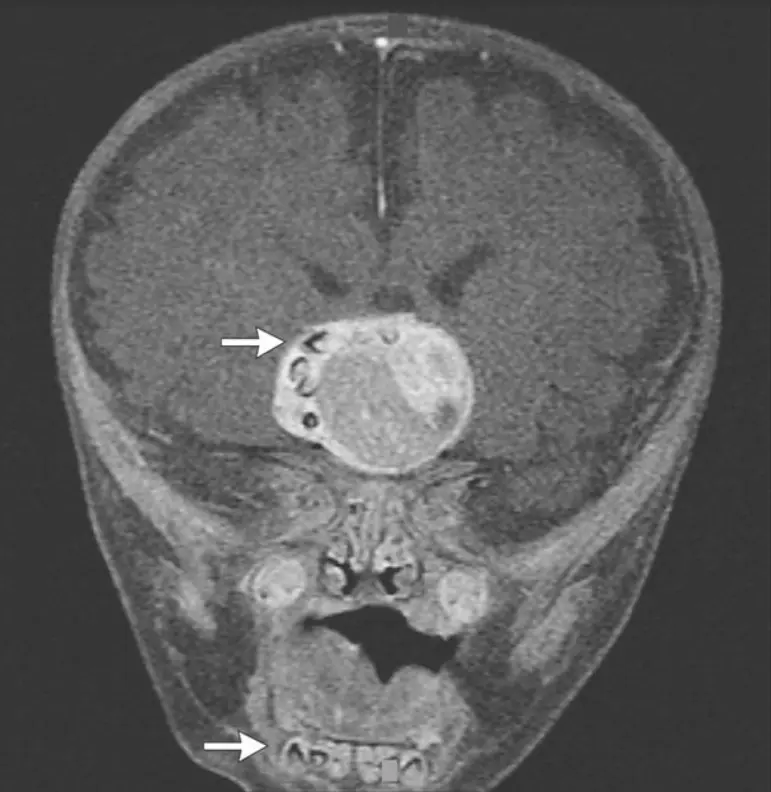

Cherchant à déterminer pourquoi le volume crânien d'un nourrisson de 4 mois augmentait avec une vitesse inhabituelle, des médecins du Maryland (Etats-Unis) ont découvert qu'une tumeur de quatre centimètres de diamètre s'était développée à proximité de son hypophyse. Au coeur de la tumeur, de petits éléments denses, vraisemblablement constitués de calcium, semblaient s'être formés. L'intervention chirurgicale destinée à extraire la tumeur a révélé que ces masses étaient... des dents, entièrement formées. Explications.

Non cancéreuses, elles peuvent être de dimension très variables. Elles ont la particularité d'être assez denses et - dans la forme qui se développe chez l'enfant - d'incorporer des fragments de kératine, des cristaux de cholestérol et du calcium (tumeur calcifiée). On parle alors de craniopharyngiome adamantinomeux (du latin adamas, qui signifie "pierre dure" ou "diamant").

Moins d'une dizaine de cas semblables sont précisément décrits dans la littérature médicale. La découverte, inédite, de plusieurs dents parfaitement formées dans une tumeur, par les chirurgiens du Maryland, apporte une nouvelle confirmation de l'hypothèse d'un calcium produit par des cellules dentaires.